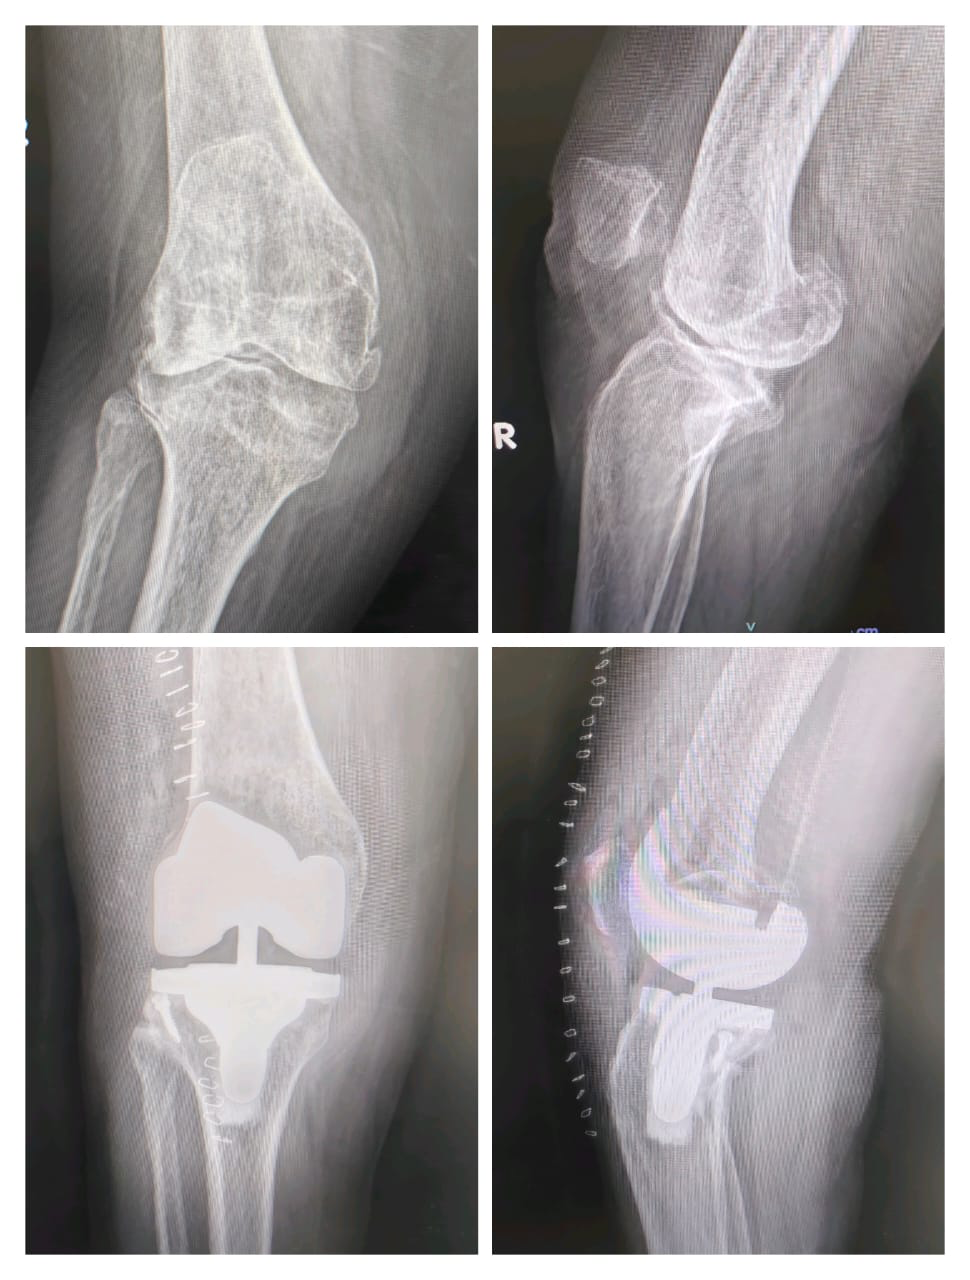

Successful Complex Primary Total Knee Replacement Surgery